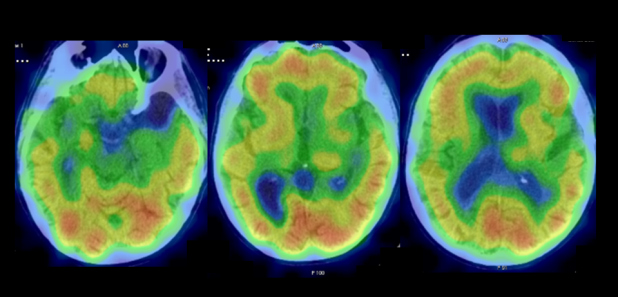

En la resonancia magnética (RM) se encontró discreto aumento del espacio extraaxial y del sistema ventricular supratentorial, secundario a atrofia parenquimatosa córtico-subcortical dependiente de la edad (fig. 1).